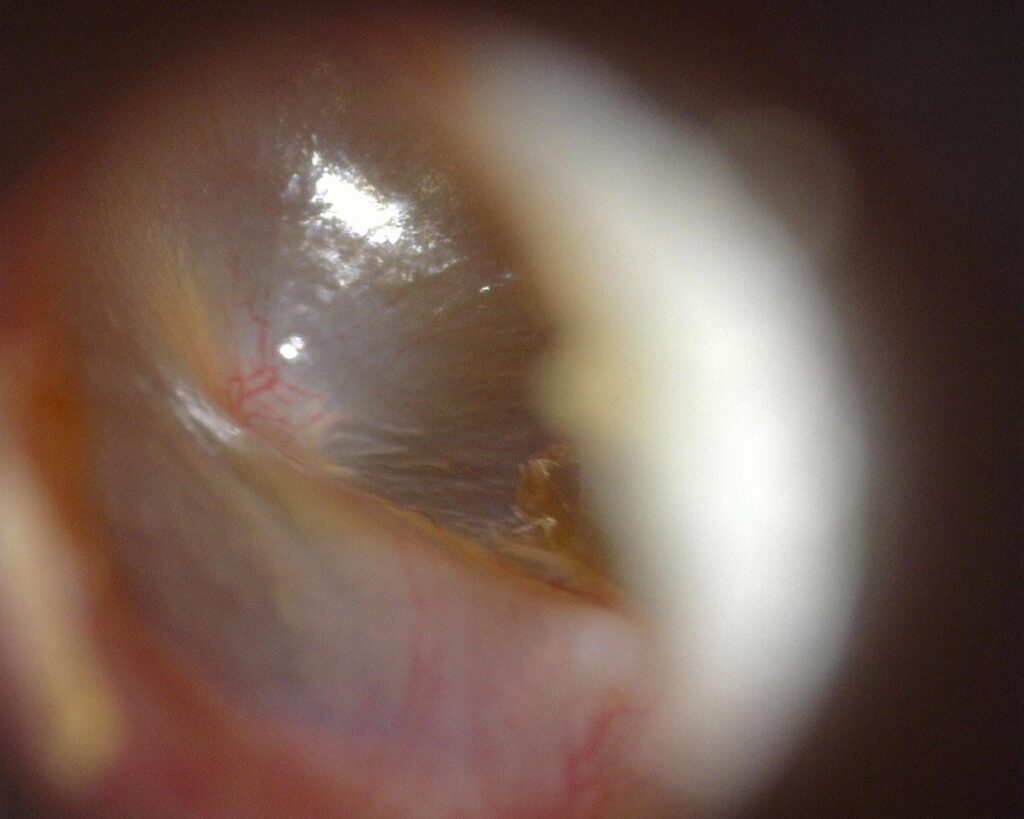

- Inspección del Canal Auditivo

Los sistemas de video-inspección portátil Dino-Lite proveen una ingeniería visual avanzada para la documentación digital de conductos estrechos. Diseñado para un soporte cómodo en el canal auditivo externo, proyectando capturas de alta nitidez en tiempo real directamente hacia computadoras, tabletas o pantallas de control en el consultorio.

Equipados con iluminación LED regulable y lentes calibrados, estos sistemas permiten registrar el micro-relieve de las estructuras anatómicas externas con claridad superior. Su arquitectura optimiza la ergonomía en la consulta general, facilitando reportes visuales instantáneos y el resguardo seguro de imágenes.